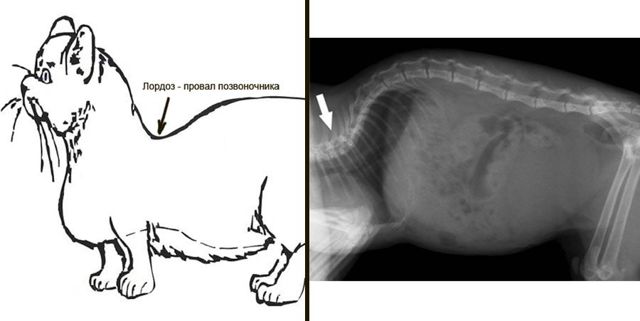

Иных заболеваний у этой породы не найдено, хотя многие специалисты считают её предрасположенной к лордозу — искривлению позвоночника, вызывающему нарушения внутренних органов.

Иногда встречаются случаи врождённого лордоза, однако он присущ всем породам и не связан с ахондроплазией, что не позволяет считать это специфической болезнью манчкинов. Продолжительность жизни в среднем — 12–15 лет, а при должном уходе и заботе и до 20 лет.

При лордозе позвоночник опускается в грудную клетку, давит на внутренние органы и последствия могут быть самыми непредсказуемыми

Единственная проблема, с которой могут столкнуться владельцы этих малышей, — это лордоз: заболевание, при котором ослабляются околопозвоночные мышцы, что приводит к деформации позвоночника. Это может вызвать сбой в работе внутренних органов.

Тяжелая форма лордоза приводит к гибели животного в раннем детстве. Информации, которая подтверждала бы связь возникновения этого заболевания с геном коротколапости, нет. Лордоз встречается у кошек разных пород.